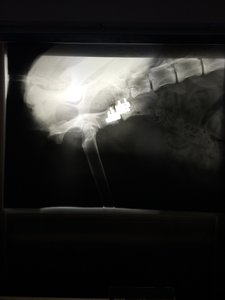

Ich hab mir mal die Röntgenbilder schicken lassen.

Hier sieht man mal den Spalt der nach dem Sturz entstanden war man sieht auch, wie sehr der Beckenknochen in Richtung Wirbelsäule gedrückt wurde :shock:

Hier mal im direkten Vergleich: direkt nach der OP

So sieht es jetzt aus. Knochenmaterial noch etwas "dünn", aber jetzt schon soweit, dass sie absolut nicht mehr humpelt oder hoppelt und auch wieder komplett belastet.

Ich find's halt so krass, wie weit nach innen sich das Becken verschoben hat :shock:

Aber der Chirurg meinte, dass es kein Problem darstellt, so lange sie nicht trächtig wird, aber das Thema hat sich ja eh erledigt...